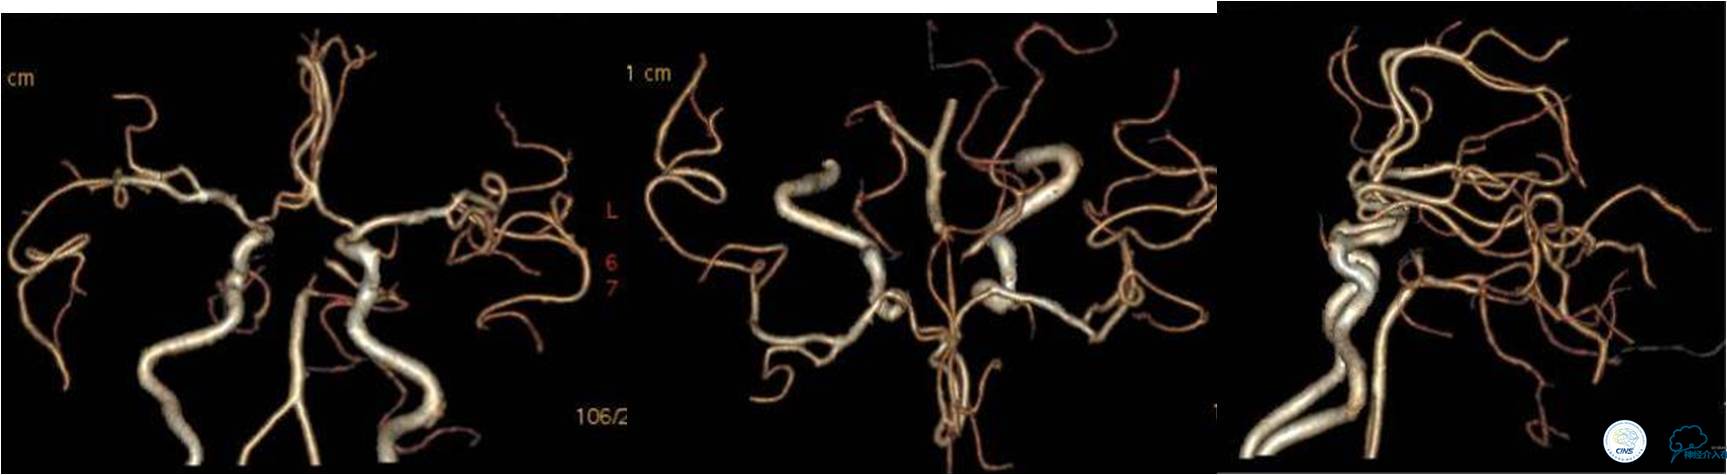

》DSA资料(左侧颈动脉)

》DSA资料(右侧颈动脉)

》DSA资料(左侧椎动脉)

》DSA资料(右侧椎动脉)

》DSA资料(经桡动脉,5F导引导管)

》DSA资料(前2次取栓,未取出,soli 4-20)

》DSA资料(第3次取栓)

第3次取出血栓

》DSA资料(第3次取栓后,发病10h)

》DSA资料(观察30min后,左椎造影)